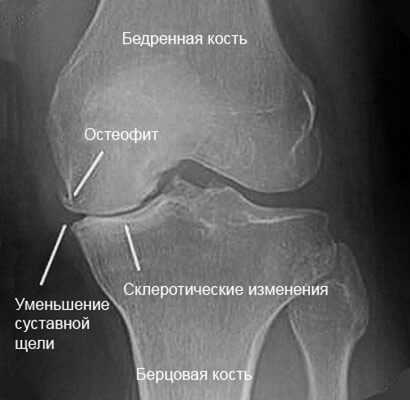

Если у пациента травмированы связки или сухожилия, межсуставная щель на изображении будет увеличена. При артрите ближайшие костные пластинки истончены, щель увеличена. Иногда на изображении толщина хрящевой прослойки сужена, кости увеличены и деформированы по краям, что показывает наличие артроза. Сужение межсуставной щели может указывать и на повреждение мениска.